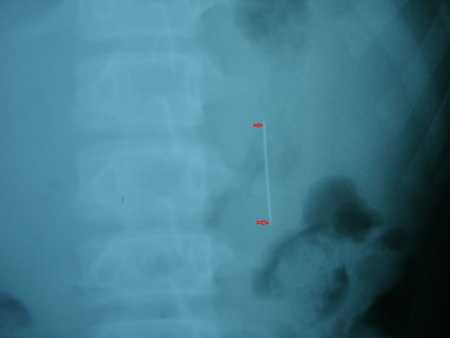

| Chiếc kim cuối cùng đã đi ra khỏi cơ thể theo đường tự nhiên |

Nên để đưa dị vật ra ngoài, các bác sĩ quyết định áp dụng biện pháp hướng dẫn cho bệnh nhân ăn nhiều chất xơ sẽ khiến cho phân chắc lại, từng bước “dìu” chiếc kim ra ngoài theo đường bài tiết, hạn chế tai biến.

Sau một thời gian kiên trì với liệu pháp ban đầu, cuối cùng chiếc kim đã di chuyển dọc theo thành ruột non và được thải an toàn ra ngoài.